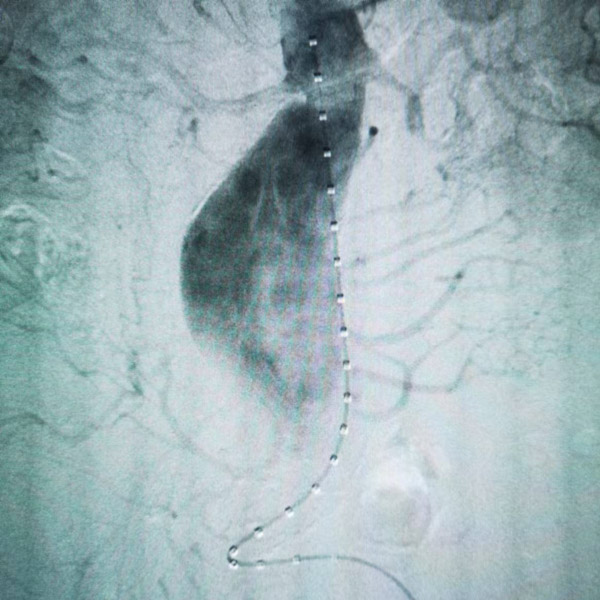

术中,血管外科手术团队参考术前CTA等影像学资料精确计算左肾动脉开口,行左肾动脉预开窗,然后在腹主动脉内,精确将支架的开窗与左肾动脉开口位置对位,准确释放,并于左肾动脉处置入肾动脉支架。

术后造影显示腹主动脉瘤完全隔绝,双侧肾动脉血流通畅,各脏器未见明显缺血,患者无腹痛,无肾功能损害,肌酐尿素氮未见升高。一星期后复查CTA显示支架位置良好,未见明显内漏,双肾动脉未见明显狭窄或闭塞。患者顺利康复出院。

血管外科手术团队经多学科会诊后,决定先行冠脉造影及脑血管造影评估手术风险。评估后,决定为患者行双肾动脉体外预开窗+腹主动脉腔内修复。术中先行双肾动脉体外预开窗,然后在腹主动脉内,精确将支架的双开窗与双肾动脉开口位置对位,准确释放支架,并于双肾动脉处置入肾动脉支架。

术后造影显示腹主动脉瘤完全隔绝,双侧肾动脉血流通畅。一星期后复查CTA显示支架位置良好,未见明显内漏,双肾动脉未见明显狭窄或闭塞。